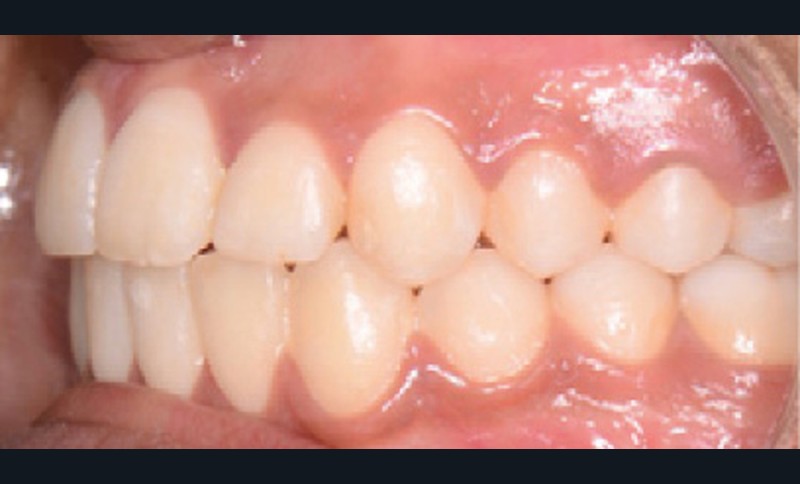

Sur le plan dentaire, elle présente une classe II d’Angle complète, une supraclusion de 4 mm et un surplomb de 6 mm ne correspondant pas au décalage de classe II molaire.

Nous avons pu repositionner l’incisive mandibulaire de 8° (fig. 10), obtenir un surplomb correspondant à la classe II d’Angle et ainsi réaliser l’avancée mandibulaire. Le chirurgien accompagne celle-ci d’une génioplastie afin d’harmoniser le profil. Nous corrigeons la DDD par stripping des incisives mandibulaires ce qui permet de corriger encore de 1° l’axe incisif.

Le résultat de fin de traitement est satisfaisant. Le profil de la patiente est harmonisé. Une contention fixe mandibulaire et maxillaire de canine à canine est choisie.